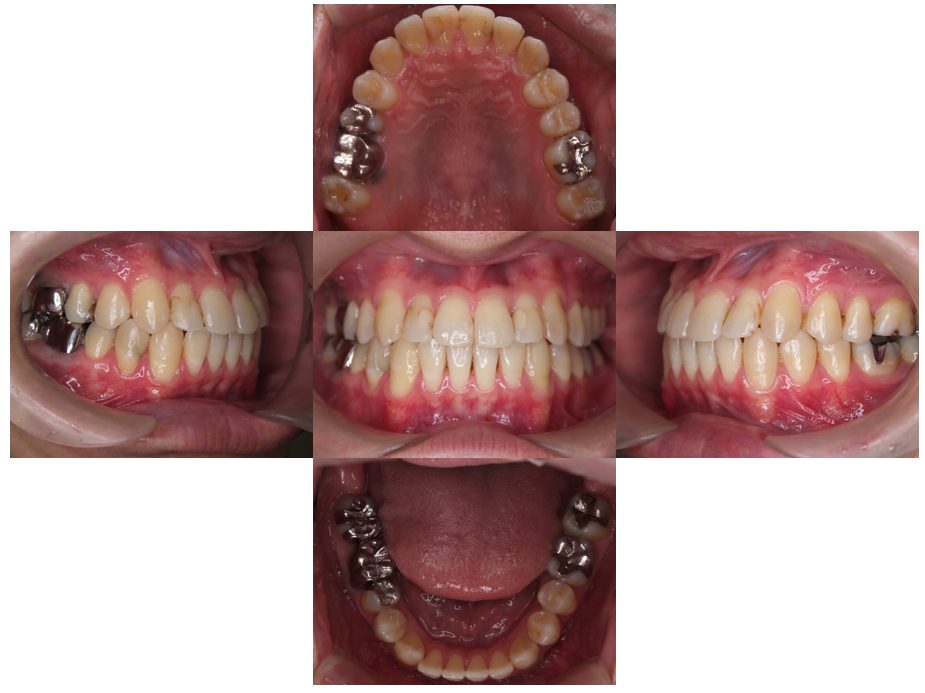

| 主訴 | 過去作成した右下の被せ物がずれて入っており、たまに腫れる。歯並びも気になる。 |

| 治療内容 | 矯正治療を行いました。 |

| 治療費 | 800,000円(税込み) |

| 治療期間 | 2年半(矯正治療期間 2年) |

| 治療回数 | 30回 |

| 想定されたリスク | 術前に基礎資料を整え分析し、セットアップモデル等でシミュレーションをしておかないと、予定通りの治療が行えないリスクがあった。 |